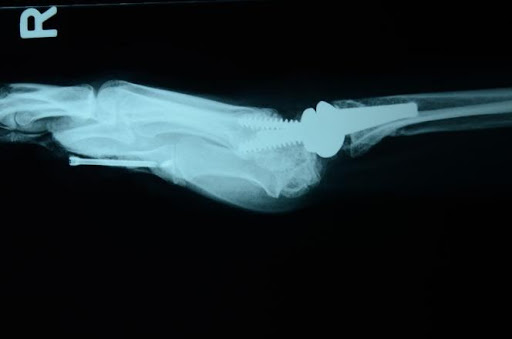

Skafolunat ekleminin ayrıldığını gösteren bileğin stresli görünümü

Aşağıda gösterildiği gibi, instabiliteyi sabitlemek için volar ve dorsal ligamanın skafolunatını tendon grefti ile yeniden yapılandırmak genellikle tercih edilen prosedürdür.